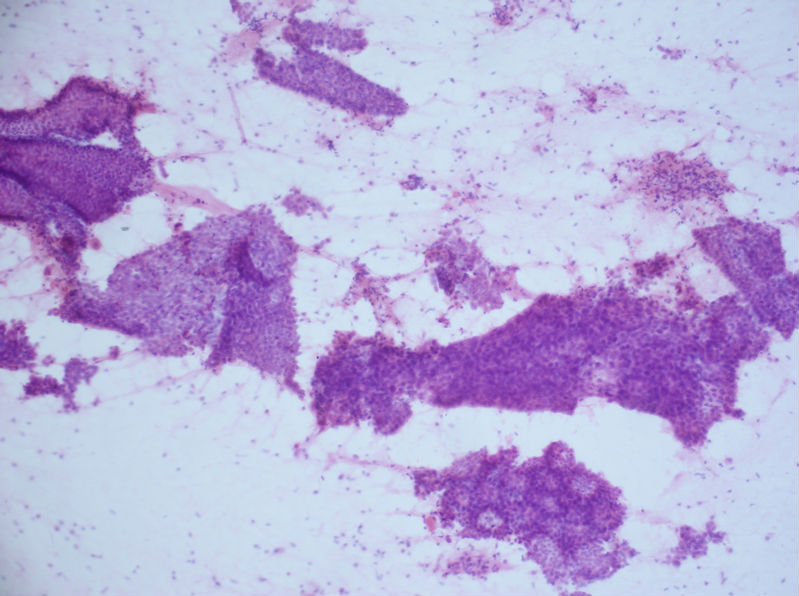

女性,44岁,左乳肿块大小3×3.5.病例分享——女性,乳腺肿块穿刺。图1

细胞腊块中能明显的看到分叶状肿瘤的间质,及刷孔状的上皮细胞。我同时做了肌上皮的标记,大部分导管上皮间阴性。

最后肿块切除:组织学诊断:(左乳)分叶状肿瘤伴导管上皮不典型增生,部分区原位癌变。

我同样在涂片的同时,制作了细胞腊块:

这例我们首先看到非常致密的间质细胞,细胞极性混乱,而且病人年龄44岁,所以首先考虑分叶状肿瘤。

这例的难点在于上皮细胞,虽然大部分上皮细胞细胞较平铺,但必须要注意到一点,大部分上皮巢团内缺乏肌上皮细胞(这点在乳腺穿刺诊断中非常重要,许多分化良好的ADH甚至DCIS或癌,细胞可以很温和,排列很平铺,最大的特点就是缺乏肌上皮细胞),同时我们还能在第5张中看到刷孔状结构,而且其内没有双极裸核的肌上皮细胞,所以这例上皮是由不典型增生的,有无癌变不敢肯定。

所以当时的穿刺涂片:考虑分叶状肿瘤伴导管上皮不典型增生,癌变难以除外。